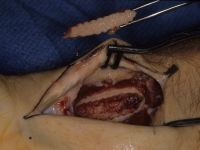

| Graft in place. Exposure facilitated by using 25 gauge needles to convert a Heiss to a Gelpi retractor. |